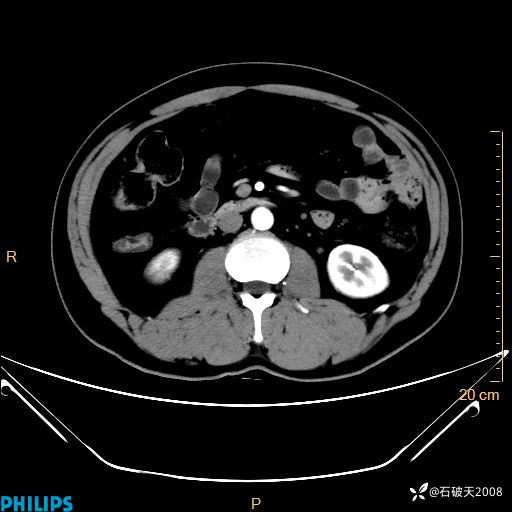

增强轴位